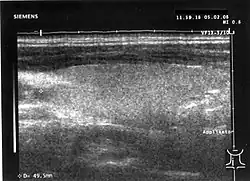

Sonografie

In der bildgebenden Diagnostik wird zunächst der Ultraschall eingesetzt. Es wird für die Schilddrüse der Einsatz von Realtime-Geräten empfohlen. Die Sendefrequenz des Schallkopfes sollte eine Mittenfrequenz 7,5 MHz nicht unterschreiten; eine bessere Detailauflösung insbesondere in oberflächennahen Strukturen bieten Schallköpfe mit einer höheren Sendefrequenz von bis zu 13,5 MHz. Neue Geräte bieten zum Teil höhere Sendefrequenzen bis 17 MHz (Stand 2010). Eine Bildbreite von etwa 6 cm erlaubt in der Mehrzahl der Fälle von vergrößerter Schilddrüse die Bestimmung des Gesamtdurchmessers; Linearschallköpfe mit größerer Bildbreite können die Untersuchung bei Patienten mit kurzem Hals erschweren.

Mit der Sonografie kann die Ausdehnung der Schilddrüse in den drei Raumachsen gemessen und daraus das Volumen berechnet werden (Ellipsoid: Länge mal Höhe mal Breite mal 4/3 mal Pi geteilt durch 8; näherungsweise beträgt das Volumen (in ml) Länge mal Höhe mal Breite (jeweils in cm) geteilt durch 2). Die Schilddrüse hat bei der Frau ein normales Volumen von etwa 6 bis 18 ml, beim Mann von etwa 9 bis 25 ml. Eine vergrößerte Schilddrüse wird als Struma bezeichnet. Beim Morbus Basedow ist das Organ meist vergrößert, bei der Hashimoto-Thyreoiditis in der hypertrophen Form normal groß oder vergrößert, in der atrophen Form (Ord-Thyreoiditis) verkleinert. Eine Zungengrundstruma sowie eine mediane Halszyste, die versprengtes Schilddrüsengewebe enthalten kann, können oft dargestellt werden. Auch eine teilweise hinter dem Brustbein gelegene (retrosternale) Struma kann oft zumindest teilweise in ihrer Größe erfasst werden. Die Messabweichung des Schilddrüsenvolumens liegt zwischen 10 und 30 %. Je größer die Schilddrüse ist, desto weniger genau lässt sich das Messergebnis reproduzieren.

Abweichungen im sonografischen Grundmuster finden sich bei den Autoimmunerkrankungen der Schilddrüse; das Organ erscheint oft inhomogen oder echoarm. Herdbefunde (Knoten, Zysten) werden in ihrer Größe, Lage und Art der Randbegrenzung beschrieben. Autonome Adenome haben oft einen echoarmen Randsaum. Ein inhomogen-echoarmer und unscharf begrenzter Knoten ist verdächtig auf das Vorliegen eines Schilddrüsenkarzinoms, zusätzliche Verkalkungen in diesem Knoten können ein Hinweis auf ein medulläres Schilddrüsenkarzinom sein. Zysten sind echofrei und zeigen auf ihrer Schallkopf-abgewandten Seite eine (scheinbare) Schallverstärkung.

Die farbcodierte Doppler-Sonografie gibt zusätzliche Hinweise auf die Art der Schilddrüsenerkrankung. Eine diffus vermehrte Durchblutung findet sich beim Morbus Basedow, oft auch bei der Hashimoto-Thyreoiditis. Der echoarme Randsaum des autonomen Adenoms entspricht im Doppler-Sonogramm einer randständig vermehrten Durchblutung. Eine Differenzierung zwischen gutartigen und bösartigen Knoten gelingt auch mit dieser Methode nicht mit Sicherheit; gleiches gilt für die Szintigrafie.